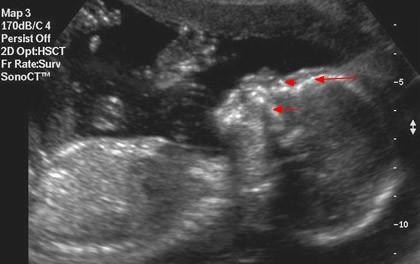

Plod 21. týden těhotenství. Pohled z boku dokumentuje vyrovnávání disproporcí mezi mozkovou a obličejovou částí hlavičky. Nejdelší šipka označuje čelo, před ní krátká nosní kůstku a spodní šipka ukazuje na horní čelist. Tento týden je vhodný k provádění II. ultrazvukového screeningu. V oblasti zad se ostře rýsují jednotlivé obratle.